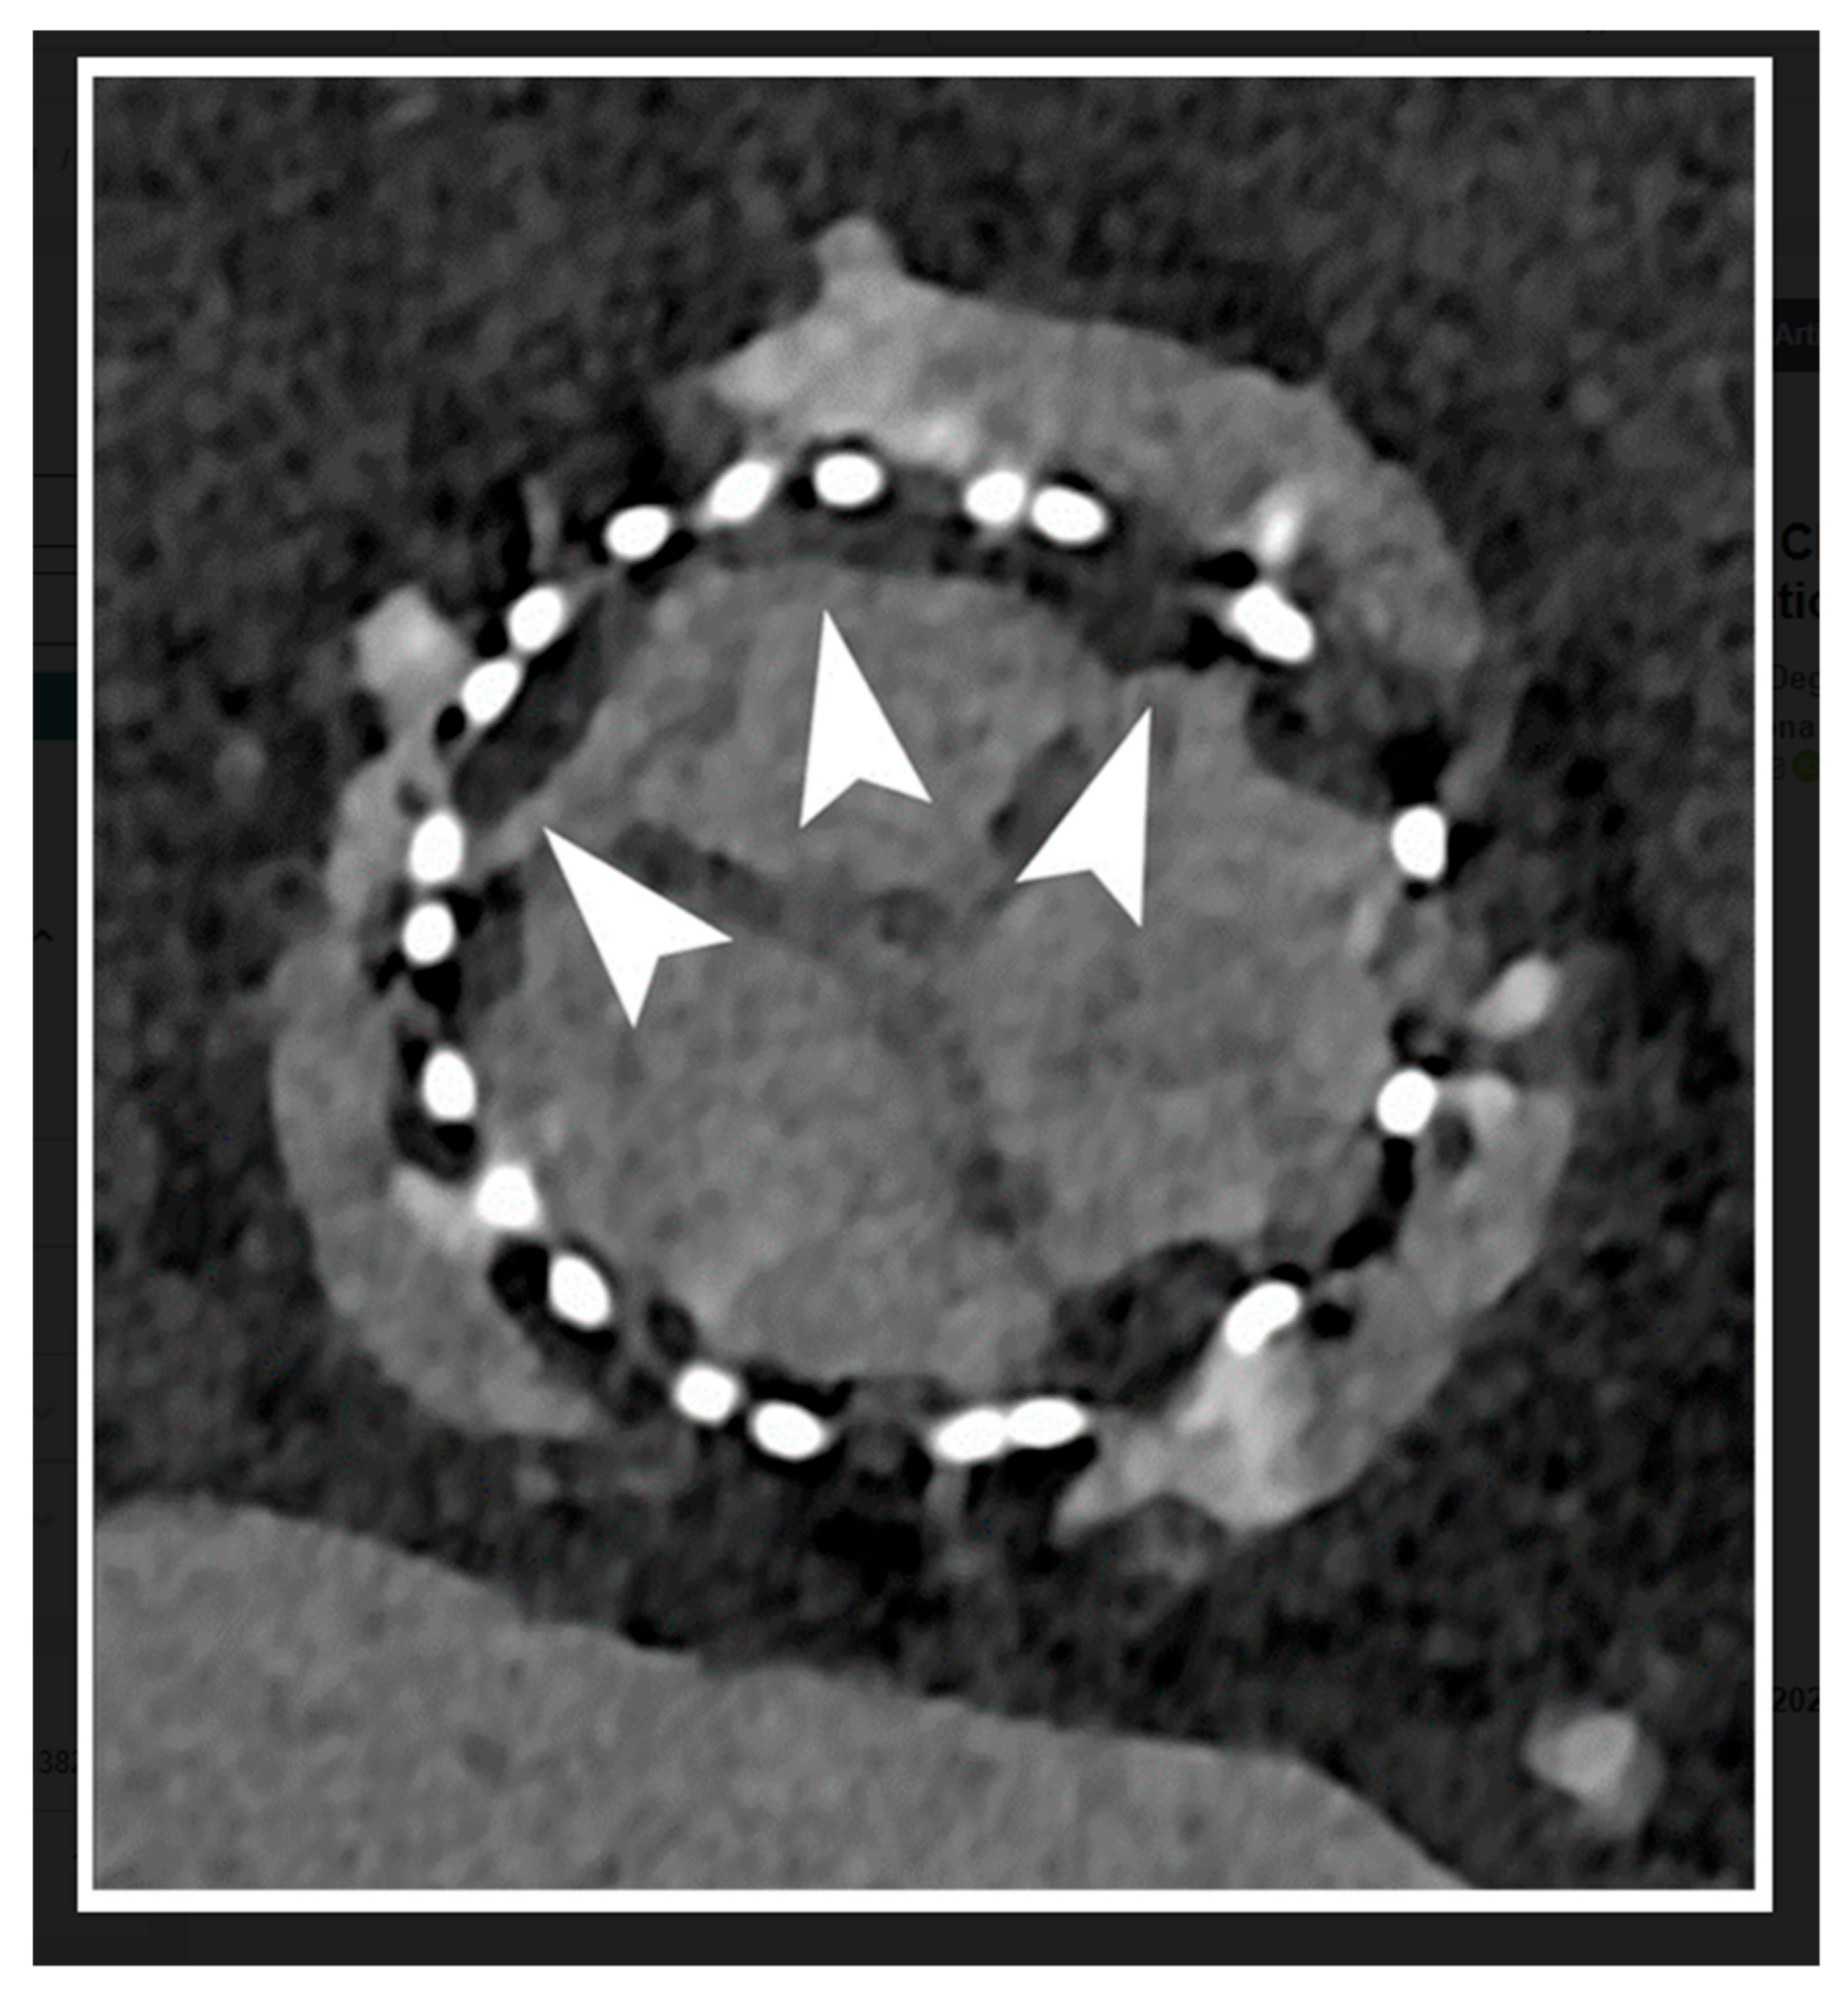

- Koons, E.; VanMeter, P.; Rajendran, K.; Yu, L.; McCollough, C.; Leng, S. Improved quantification of coronary artery luminal stenosis in the presence of heavy calcifications using photon-counting detector CT. Proc. SPIE. Int. Soc. Opt. Eng. 2022, 12031, 120311A. [Google Scholar] [CrossRef]